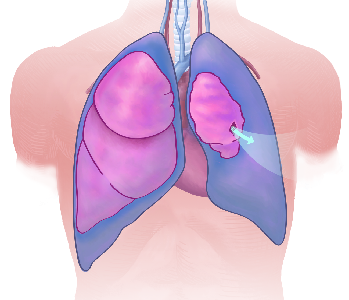

Detailreiche Fotografien aus der medizinischen Praxis ergänzen die Texte; moderne, genaue,

wissenschaftliche Zeichnungen geben Einblick in die Anatomie und die Funktion der Lunge und

anderer Organe.